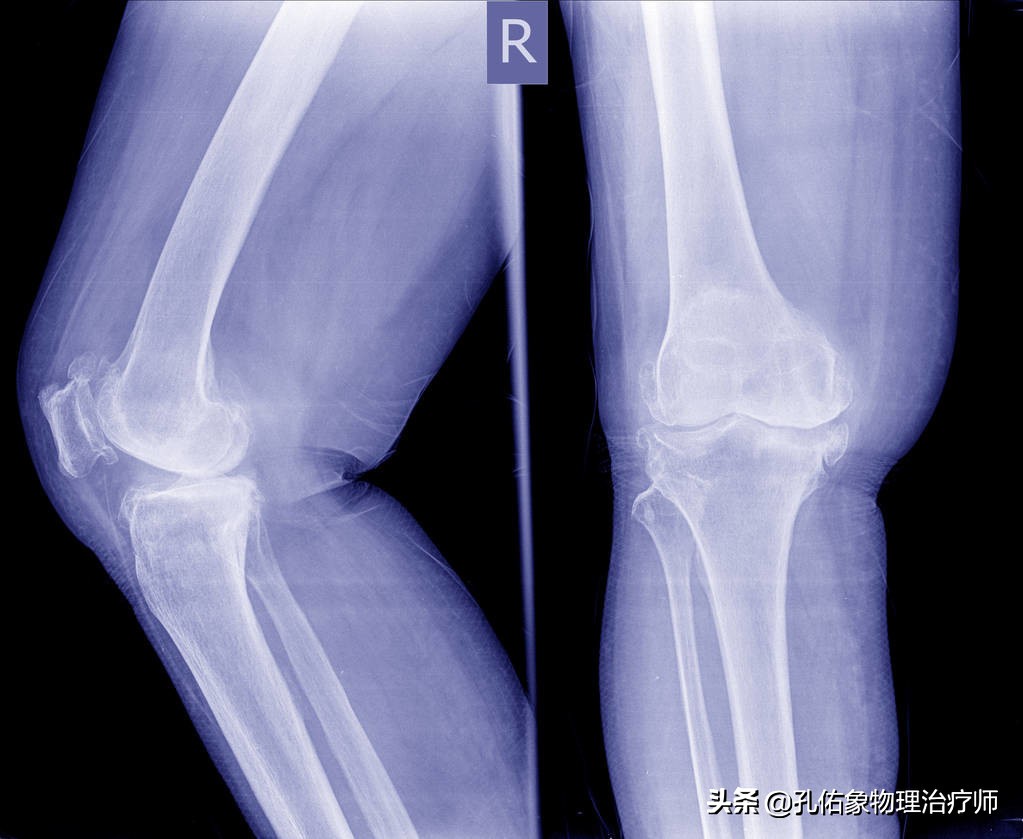

软骨一开始受到磨损,首先会出现水肿;随着膝关节应力的变化,软骨就会慢慢变薄,呈现出纤维化;再随着关节的使用,纤维化越来越重,就会表现出X片下的关节边缘的骨赘物;最后就会使得软骨的全层缺损,裸露出软骨下面的骨质。在负重行走时产生膝部的疼痛,因疼痛,膝关节的活动量就不得不减少,慢慢的膝关节就会活动非常不灵活,甚则关节僵直,就像汽车的轴承生锈一样,恶性循环,最终发展为膝关节骨性关节炎,关节间隙的变窄,关节变形,活动丢失。如下图所示:

软骨软化结果

- 拍片来判断

首先可以拍一个X片,只是这个X片的拍摄很有讲究,需要轴位片。因为很多人,在出现膝关节疼痛早期,软骨软化早期,在正侧位上的X片是看不出软骨的问题的,除非是老年人那种膝关节已经严重丢失活动时,才能在一般的X片上得以体现。

而轴位X片,刚好可以看膝盖骨与大腿骨之间的变化,有没有在正常的轨迹里边?做这个检查时,要求患者在下蹲的过程中,出现疼痛时侯的角度来拍片,结果膝盖骨要是外移的话,就是典型的髌骨软骨软化的表现。如下图所示:

膝轴位X片